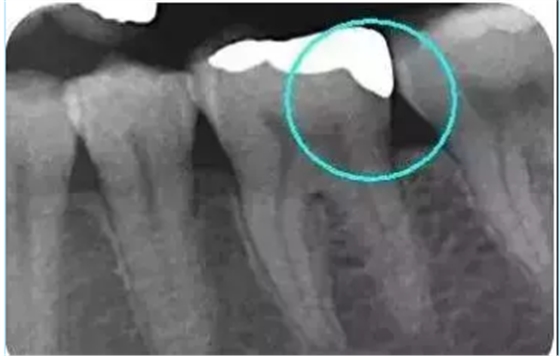

從下面這張X線中可以看出,嵌體遠(yuǎn)中邊緣沒(méi)有懸突,與牙體邊緣密合相接。